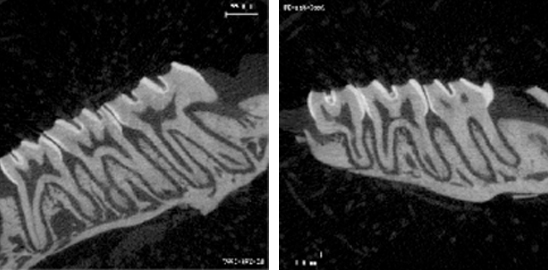

1. 小鼠牙齒高清影像圖

0001